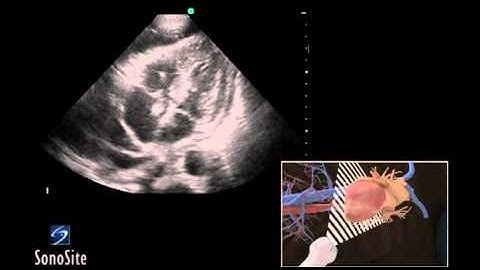

3D How To Subxiphoid View, Echocardiography